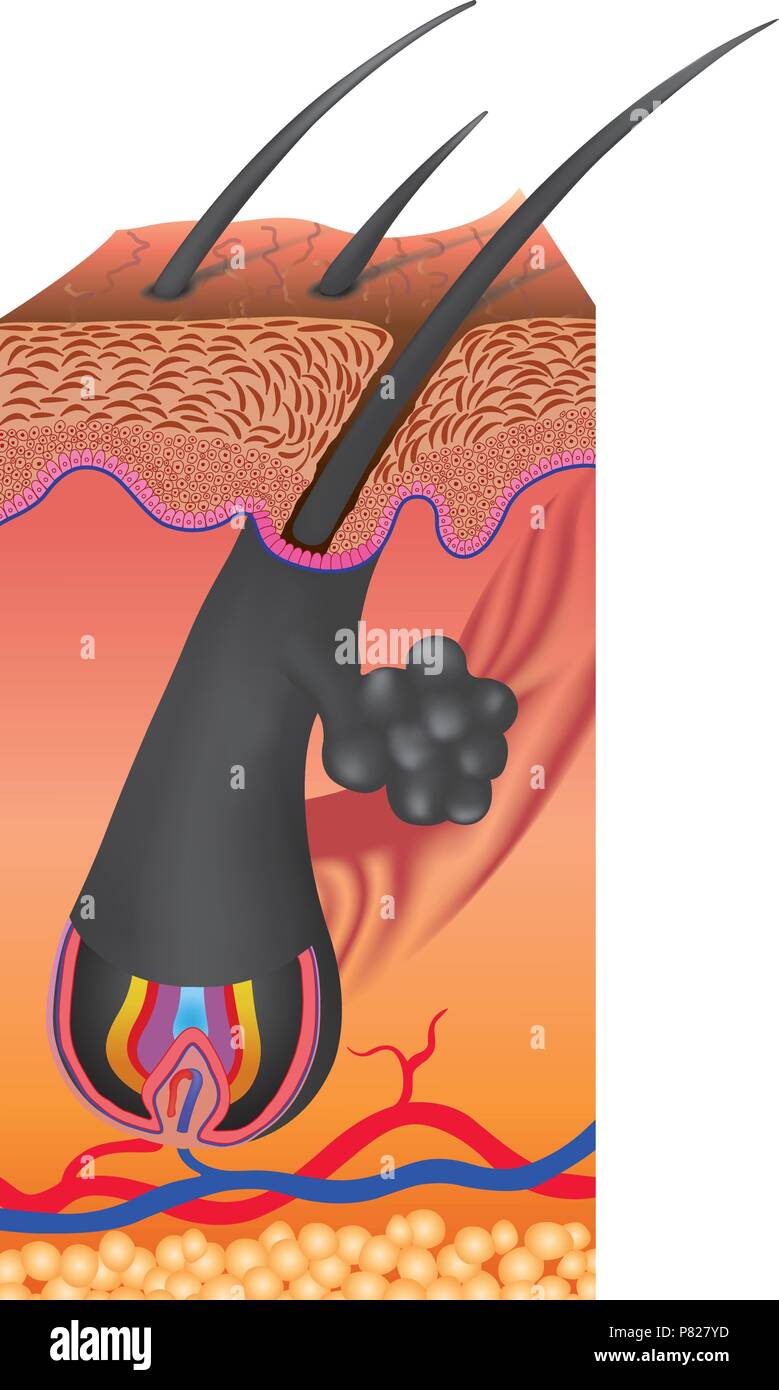

Capelli segue un determinato ciclo di crescita con tre distinti e fasi contemporanee anagen e catagen e telogen fasi Illustrazione Vettorialehttps://www.alamy.it/image-license-details/?v=1https://www.alamy.it/capelli-segue-un-determinato-ciclo-di-crescita-con-tre-distinti-e-fasi-contemporanee-anagen-e-catagen-e-telogen-fasi-image211491825.html

Capelli segue un determinato ciclo di crescita con tre distinti e fasi contemporanee anagen e catagen e telogen fasi Illustrazione Vettorialehttps://www.alamy.it/image-license-details/?v=1https://www.alamy.it/capelli-segue-un-determinato-ciclo-di-crescita-con-tre-distinti-e-fasi-contemporanee-anagen-e-catagen-e-telogen-fasi-image211491825.htmlRFP827YD–Capelli segue un determinato ciclo di crescita con tre distinti e fasi contemporanee anagen e catagen e telogen fasi

Capelli segue un determinato ciclo di crescita con tre distinti e fasi contemporanee anagen e catagen e telogen fasi. Ogni fase ha specifici characteri Illustrazione Vettorialehttps://www.alamy.it/image-license-details/?v=1https://www.alamy.it/foto-immagine-capelli-segue-un-determinato-ciclo-di-crescita-con-tre-distinti-e-fasi-contemporanee-anagen-e-catagen-e-telogen-fasi-ogni-fase-ha-specifici-characteri-135200016.html

Capelli segue un determinato ciclo di crescita con tre distinti e fasi contemporanee anagen e catagen e telogen fasi. Ogni fase ha specifici characteri Illustrazione Vettorialehttps://www.alamy.it/image-license-details/?v=1https://www.alamy.it/foto-immagine-capelli-segue-un-determinato-ciclo-di-crescita-con-tre-distinti-e-fasi-contemporanee-anagen-e-catagen-e-telogen-fasi-ogni-fase-ha-specifici-characteri-135200016.htmlRFHRXW00–Capelli segue un determinato ciclo di crescita con tre distinti e fasi contemporanee anagen e catagen e telogen fasi. Ogni fase ha specifici characteri